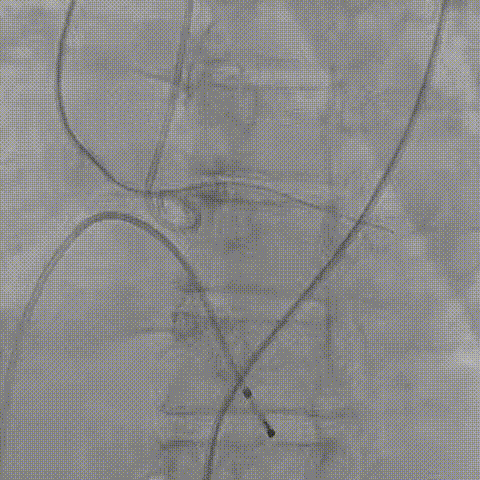

患者病史 主诉:发作性胸闷憋喘半年,加重伴呼吸困难2周。 现病史:患者半年前无明显诱因出现胸闷、憋喘,伴有下肢水肿,2周前上述症状明显加重,夜间不能平卧,痰中带血丝,为进一步诊治再次来我院,门诊以"心力衰竭"收入院。 既往史:肾功能不全、心房颤动 心脏超声提示:LVEF:0.54 1.主动脉瓣病变;2.主动脉瓣狭窄(重度)并反流(中度);3左室壁节段性运动不良;4.升主动脉扩张、双房扩大、左室肥厚;5.二尖瓣硬化并反流(中度);6.三尖瓣反流(轻-中度);7.肺动脉瓣反流;8.肺动脉高压(轻度)PGmean=105mmHg,Vmax=635cm/s,瓣口面积0.27cm²。 术前CT评估 Type0型二叶瓣,重度钙化,钙化集中在瓣叶游离缘,右冠窦为著;左冠高度11.8mm,由于左冠窦部空间较小,左冠风险较高, 升主动脉扩张,最宽处50.5mm;主动脉瓣环水平夹角61.5°,横位心。主动脉弓角77.6°,锐角弓,外周入路在腹主及髂总处有大量散状钙化,胸主处有81.6°的迂曲。 手术策略 推荐右侧股动脉为主入路,左侧股动脉为辅入路,送snare辅助过弯,使用18F大鞘,推荐预装ProStyle A® AV23瓣膜,20mm球囊预扩,初始定位对齐真实瓣环瓣上5mm超高位初始定位释放,释放过程中使瓣膜自然下滑,到工作位观察瓣膜形态,最终理想位置0-瓣下3mm。 手术过程 Step1:右侧股动脉为主入路、左侧股动脉为辅入路,成功穿刺并送入 18F 大鞘; Step2:主动脉根部造影,瓣口限制重 Step3:Type 0 型二叶瓣畸形合并重度钙化,患者瓣口狭窄严重,同时横位心,不仅导丝跨瓣困难,导管更难进入;术者凭借精湛操作,将导丝顺利跨瓣,反复微调导管角度,最终导管顺利过瓣。 导丝精准跨瓣 Step4:20mm球囊跨瓣困难,snare辅助下球囊成功跨瓣,预扩有腰无漏,冠脉充盈良好。 Step5: snare辅助下成功跨瓣,可以看到系统过弓形态瓣膜仓柔软,过弓顺滑 输送系统过弓 Step6:初始定位瓣上5mm开始释放,释放部分后观察瓣架下缘内收明显,后回收系统重新定位 初始定位 底部内收 Step7:瓣膜完全释放前,血压一度降低,术者迅速调整器械,实现瓣膜迅速锚定,快速释放 完全释放 Step8:20mm球囊后扩 最终造影,位置(瓣下3mm)形态良好 手术难点 患者不仅有主动脉瓣重度狭窄,还叠加肾功能不全、心房颤动等基础疾病,术中血流动力学波动极易引发心功能衰竭。ProStyle A® 预装干瓣“开包即用” 的特性压缩了术者操作时间,80%可回收设计给了术者容错空间,而这些看似难以逾越的难关,最终被团队精湛的医术一一化解,术中对于导丝、导管、球囊等器械每一步的精准操控,再到突发状况的从容处置,无不彰显着团队深厚的专业积淀与顶尖的操作技艺。 结语 此次手术的圆满成功,不仅彰显了陈玉国、李传保教授团队在复杂结构性心脏病介入治疗领域深厚的专业造诣与攻坚克难的决心,也充分验证了ProStyle A®系统在应对复杂高难度病例时的卓越适用性与有效性。 作为扎根齐鲁、享誉全国的医疗高地,山东大学齐鲁医院始终赓续着这片热土的仁厚文脉,将“医道从德,术业求精”的院训精神镌刻在每一次诊疗实践之中。特别是在结构性心脏病诊疗领域,医院团队始终怀揣医者担当,勇攀医学高峰,不断以更前沿的技术突破,为危重患者点亮重获新生的希望。 专家简介 陈玉国 山东大学齐鲁医院(点击查看专家详细简历) 李传保 山东大学齐鲁医院(点击查看专家详细简历) · END ·

根部造影